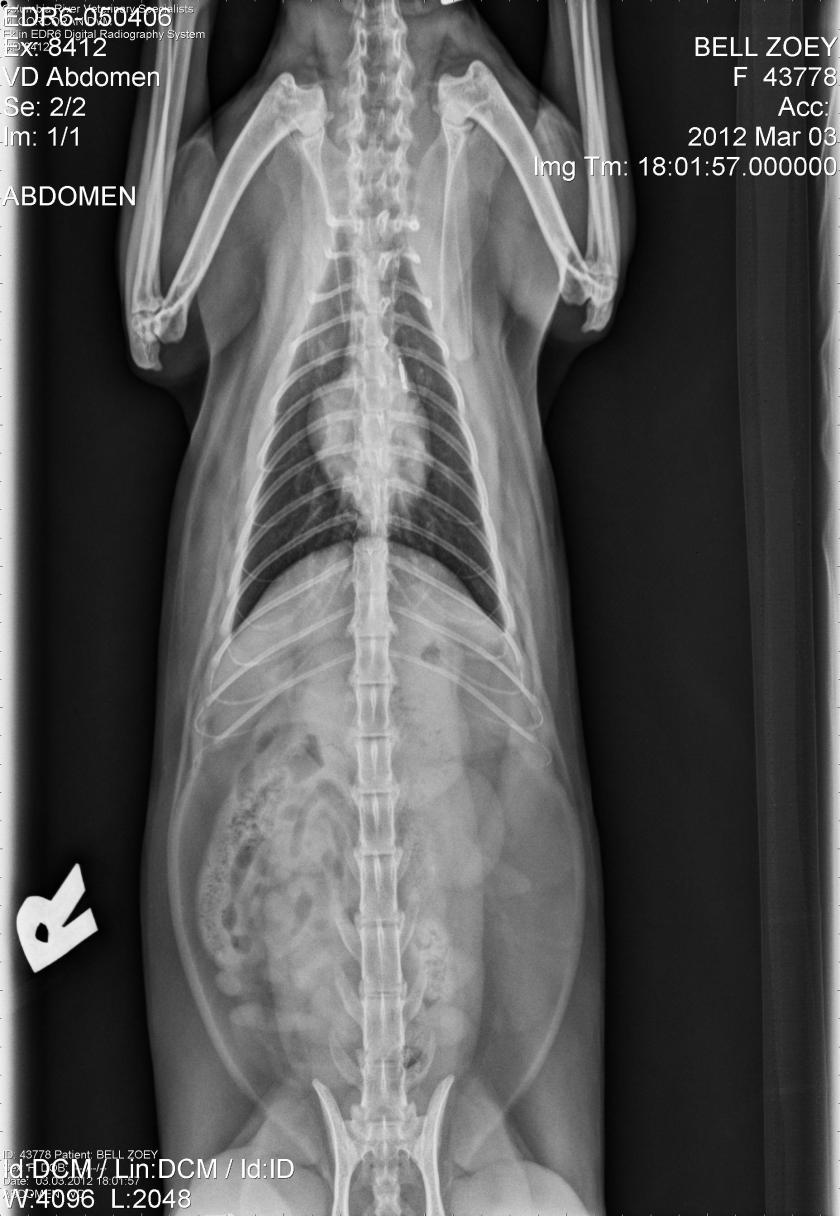

Zoey Kitty’s X-Rays!

2012, abdomen, Cat Break, Cat Stories, cat x-ray, Cats, feline, Kitties, Kitty, Kristin Bell, lateral, vet, vetrinarian, x-ray, x-raysA few weeks ago, my baby Zoey kitten had to go to the vet, because she was really sick. It turned out to be something like the flu. She had to get subcutaneous water packs and stuff, and they had to do x-rays to rule stuff out. Well, they gave me the disc with her x-rays on it, so I have her x-ray pictures to post! Pretty interesting to see! She’s doing fine now and you can see her in the last pic helping me read my book! :) Click the images for a larger viewing! :) Oh! I just noticed! In the upper left of the second image you can see her microchip!!! lol Cool!